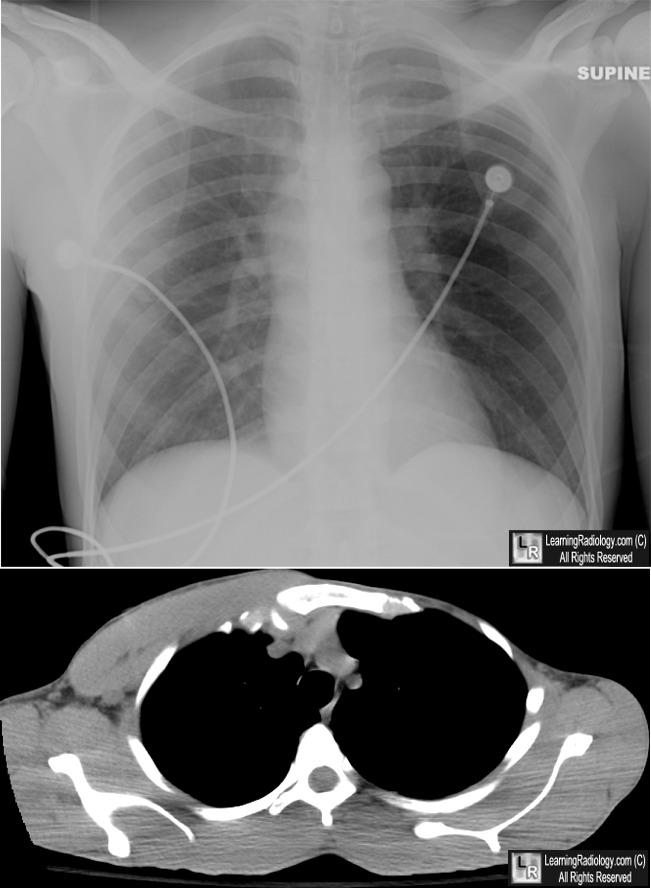

LearningRadiology - Poland, Syndrome

learningradiology.comsyndrome poland learningradiology here arrows left muscle same without click

Poland Syndrome – Radiology Cases

radiologycases.myPoland Syndrome - Stock Image - C021/1675 - Science Photo Library

radiologycases.myPoland Syndrome - Stock Image - C021/1675 - Science Photo Library

Poland Syndrome – Radiology Cases

radiologycases.myWhat Is Poland Syndrome And How To Treat It? – Healthy Food Near Me

radiologycases.myWhat Is Poland Syndrome And How To Treat It? – Healthy Food Near Me